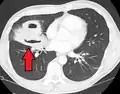

Computed tomography (CT) scan of chest showing bilateral pneumonia with abscesses, effusions, and caverns. 37-year-old male. | |

Lung abscesses are often on one side and single involving posterior segments of the upper lobes and the apical segments of the lower lobes as these areas are gravity dependent when lying down. Presence of air-fluid levels implies rupture into the bronchial tree or rarely growth of gas forming organism.

Pulmonary abscess on CT scan